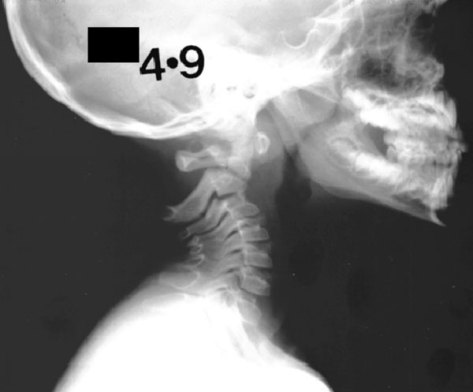

Sebuah cerita pengalaman tentang pasien yang pernah mengalami stroke namun gagal untuk ditolong akan saya paparkan. Seorang wanita mengeluh kesulitan bangun dari sujud saat sedang sembahyang karena merasa lemah pada tangan kanannya. Memang sudah sejak beberapa hari dia merasakan sakit kepala yang hilang timbul, tetapi merasa lebih enak dengan mengkonsumsi obat sakit kepala. Sang wanita kemudian menyampaikan keadaannya ini kepada tetangganya yang adalah seorang dokter bedah saraf. Dokter bedah saraf tersebut kemudian menyarankan untuk ke rumah sakit dan dilakukan beberapa pemeriksaan termasuk pemeriksaan laboratorium dan pemeriksaan pencitraan. Namun wanita tersebut beserta keluarganya menginginkan hanya untuk diberikan obat dan istirahat di rumah serta menolak untuk ke rumah sakit. Sekitar 3 jam kemudian, diketahui wanita tersebut tidak sadarkan diri dan keluarganya yang panik kemudian segera melarikannya ke rumah sakit. Dilakukan pemeriksaan CT Scan kepala emergensi dan ditemukan adanya perdarahan luas karena stroke. Usaha pertolongan yang diberikan tidak berhasil dan sudah terlambat. Wanita tersebut kemudian menghembuskan nafas terakhirnya 1 jam setelah sampai di rumah sakit.